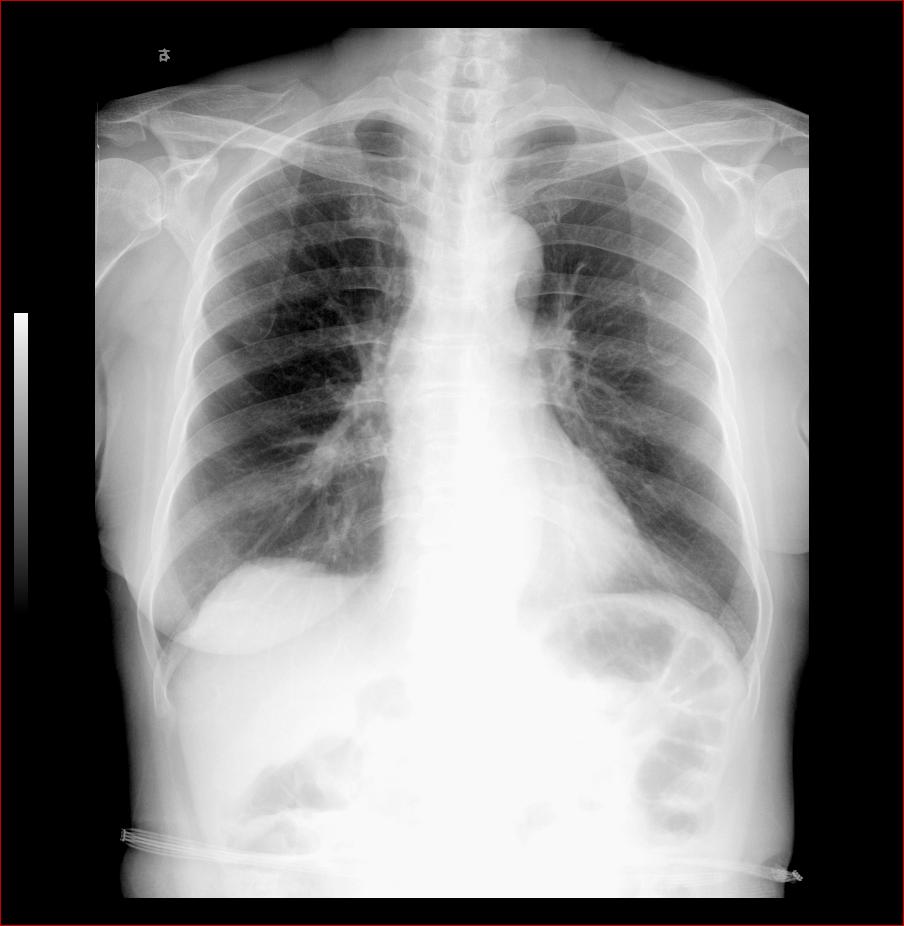

以下是引用杀毒软件在2008-3-9 20:19:00的发言:[br]如果和投照体位无关,考虑:双侧先天性高位肩胛症。

以下是引用huenhao在2008-3-9 22:45:00的发言:[br]如果和投照体位无关,考虑:双侧先天性高位肩胛症。支持